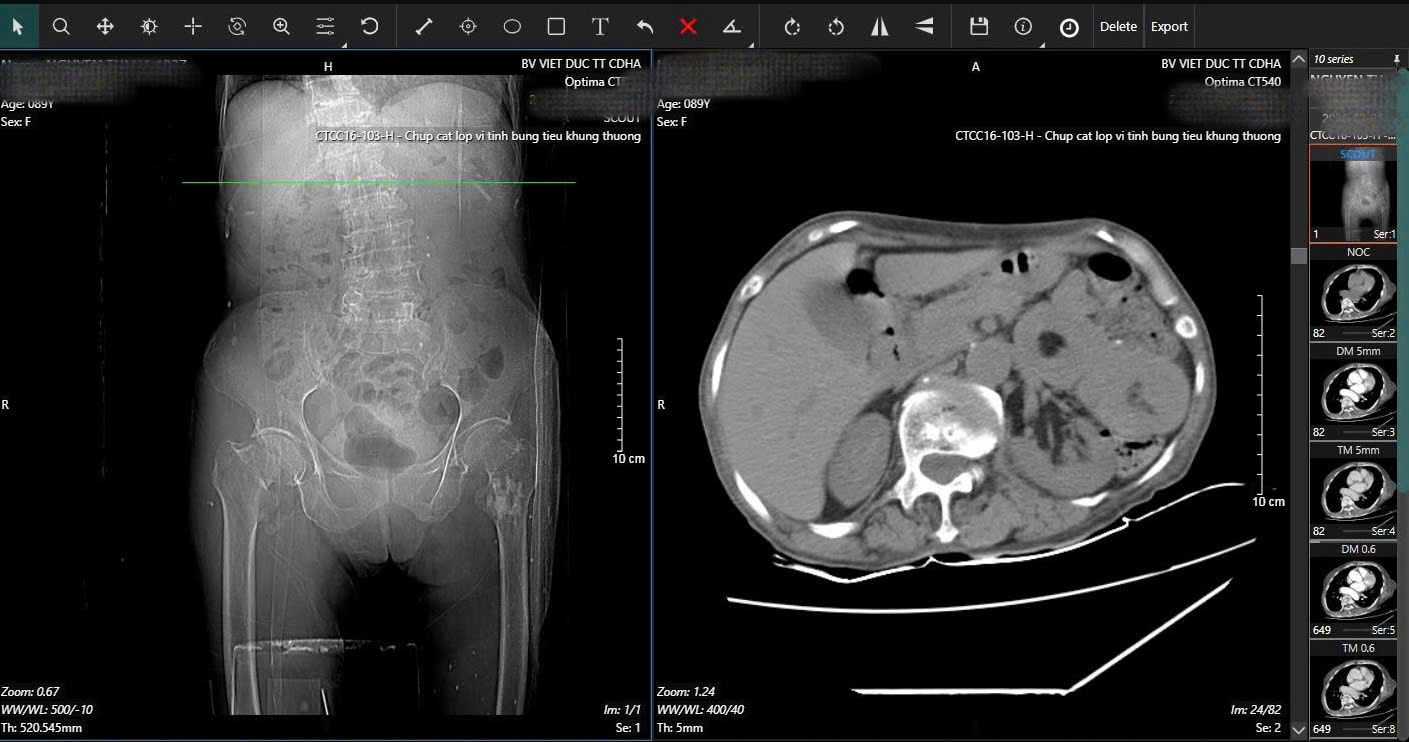

Trong quá trình kiểm tra tổng quát, các bác sĩ BV Hữu nghị Việt Đức phát hiện dấu hiệu bất thường ở vùng bụng. Kết quả chụp CT cho thấy cụ bị lồng ruột do u với khối lồng dài 165mm. Đây là tình trạng cấp cứu nguy hiểm, có thể gây tắc ruột và đe dọa tính mạng nếu không xử lý kịp thời.

Hình ảnh phim X-quang cụ bà 89 tuổi nhập viện gãy cổ xương đùi phải và hình ảnh chụp CT ổ bụng và phát hiện khối u ruột non gây lồng ruột.